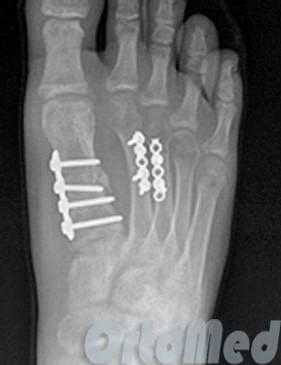

Операция при переломе плюсневой кости

Показанием к операции при переломе является смещение отломков плюсневой кости больше чем на половину ширины кости.

Открытая репозиция перелома

Открытая репозиция при переломе плюсневой кости стопы, накостный остеосинтез пластиной и винтами. Операция включает в себя хирургический разрез, доступ к сломанной плюсневой кости аккуратно отводя сухожилия, сосуды и нервы, мобилизацию костных отломков, устранение смещения и фиксация в правильном положении.

Гипсовая иммобилизация не проводится, так как металлоконструкция, фиксирует отломки.

Разрешается ходьба с опорой на пяточную область в течение месяца.